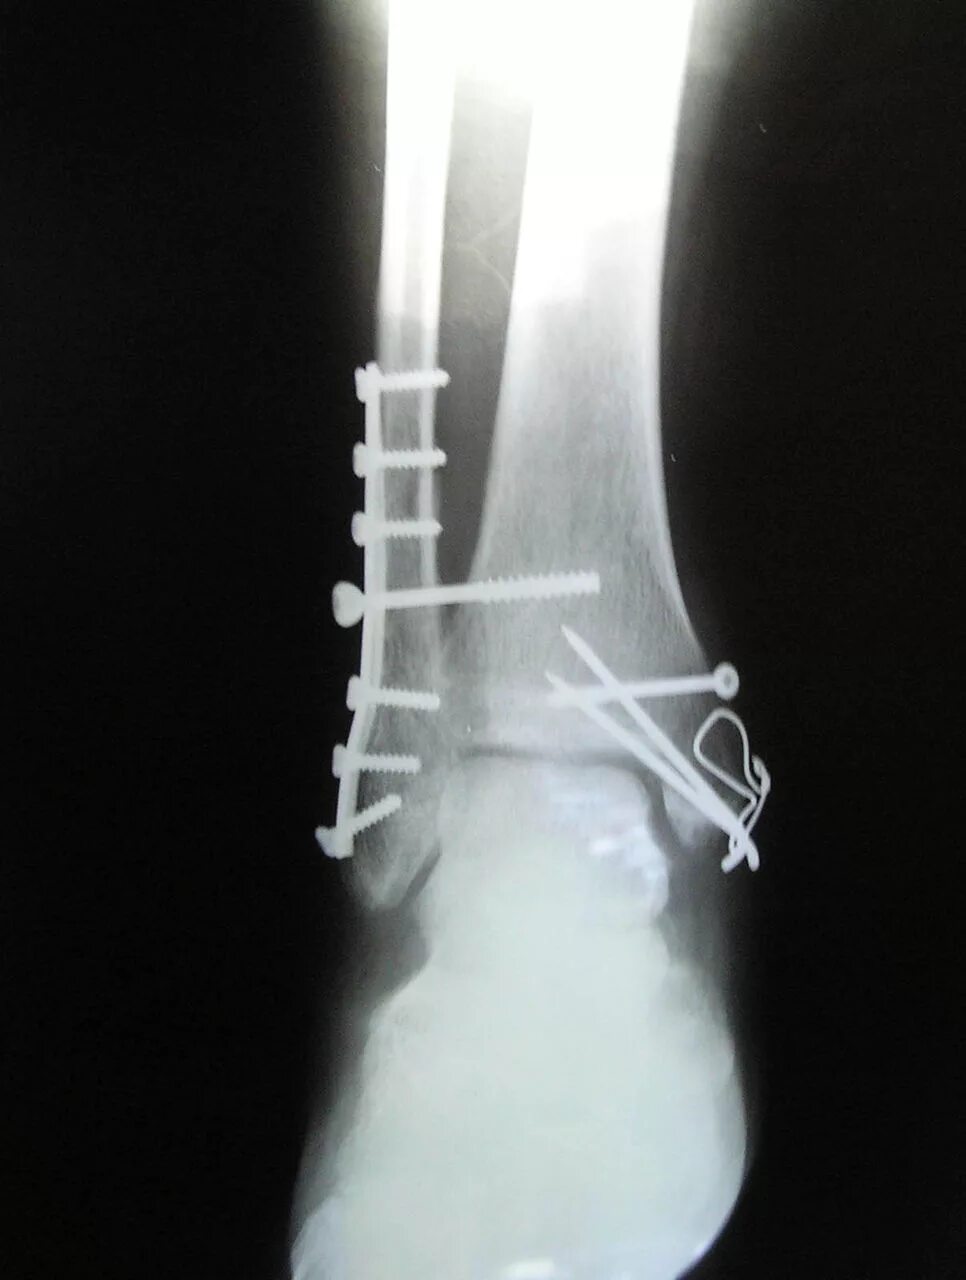

После остеосинтеза лодыжек